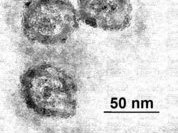

Впервые понятие неалкогольного стеатогепатита было введено в 1980 году. А уже сегодня оно признано весьма актуальным в гастроэнтерологии, поскольку его распространенность составляет от 14 до 18 процентов всего населения. Патология чаще встречается у женщин (в возрасте - 41-60 лет). Примечательно, что отсутствуют жалобы со стороны пациентов.